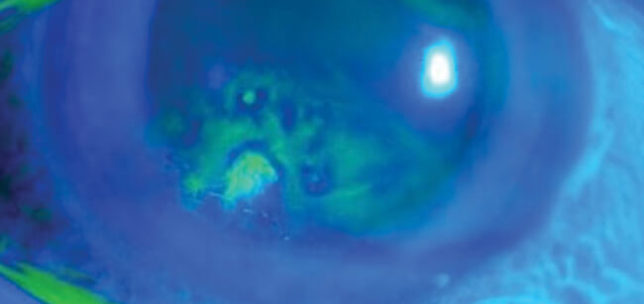

Recurrent corneal erosions secondary to isotretinoin use

Priyancaa Jeyabaladevan

·

7th December 2020

Education

Case Reports